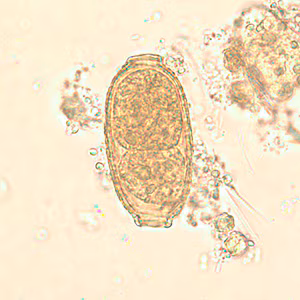

Capillaria philippinensis eggs are 35 to 45 µm in length by 20-25 µm in width, somewhat smaller than C. hepatica. They have two flat polar prominences and a striated shell. Eggs are unembryonated when passed in feces.

The specific diagnosis of C. philippinensis is established by finding eggs, larvae and/or adult worms in the stool or in intestinal biopsies. Unembryonated eggs are the typical stage found in the feces. In severe infections, embryonated eggs, larvae, and even adult worms can be found in the feces. No valid serologic testing is available for diagnosis.